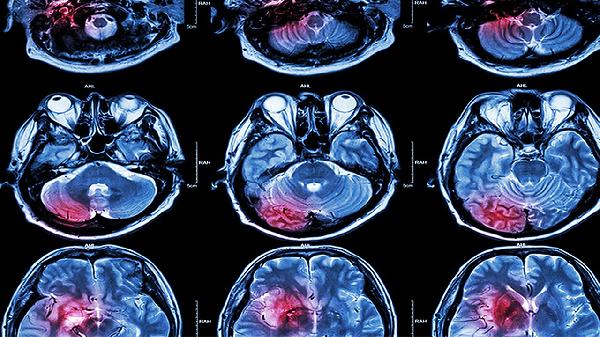

中年人脑梗死中医治疗方法

中年人脑梗死的中医治疗方法包括中药治疗、针灸治疗和推拿治疗,结合生活调理和饮食干预,有助于改善症状和促进康复。